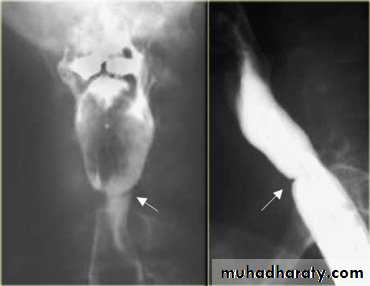

Contrast films: barium swallow is needed in the diagnosis of pharyngeal pouch, esophageal web and hypopharyngeal mass.

A chronic atrophic type of inflammation of the mucous membrane of the pharynx. The major changes occur in the postcricoid region initially started by fissuring and hyperkeratosis followed by fibrosis, web formation of stricture.

A small proportion of patients (3%) with this condition progress to the stage of postcricoid cancer.

• -Haematological: CBP---- hypochromic microcytic anaemia, low serum iron and high iron binding capacity.• -Ba -swallow: web at the

• postcricoid region.

• The condition should not be diagnosed until an organic lesions has been excluded in order not to miss an early carcinoma.• -Ba -Swallow ---- cricopharyngeal spasm